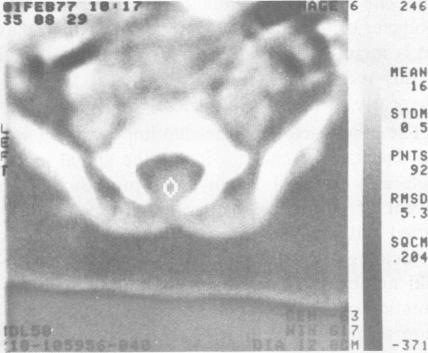

Specialty conference. Spinal dysraphism: an interdisciplinary diagnostic approach.

West J Med. 1978 Dec;129(6):475-9.